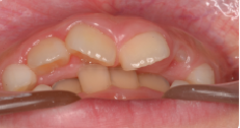

●大きく削ってインレーを詰めても細菌の取り残しがある→数年後、虫歯の再発

●大きく削ることで、別の痛みが引き起こされる場合がある

●削った部分がむき出しのまま、うがいをさせる。唾液で汚染される→さらなる虫歯や神経の炎症を起こす